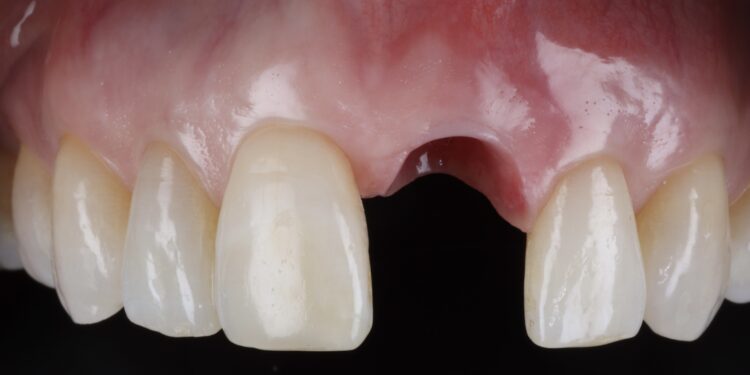

Once the orthodontic treatment was completed, the site was re-evaluated, and it was clear to see that the gingival zenith had significantly improved. The patient was advised that without re-contouring the mesial aspect of the contralateral central incisor there would be a midline black triangle. She rejected the option of composite addition to alter the triangular shape of the UR1 and thus we proceeded to complete the treatment without this. The implant was placed with simultaneous buccal GBR & connective tissue graft following a transmucosal approach. Following a healing period of 4 months, the restorative treatment was initiated with a temporary crown to develop the emergence profile. Once the gingival zeniths had been matched, the patient was delivered a permanent screw retained crown.

This case demonstrates the power of ridge preservation whereby significant hard tissue grafting was avoided entirely in a patient with an extremely thin maxillary alveolus. The improvement in soft tissue contours is evident to be seen even with a healing period of 18 months post extraction with excellent keratinised tissue volume and no distortion in the mucogingival junction.